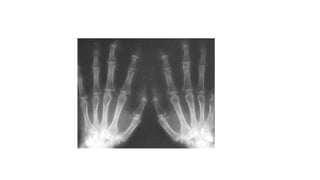

Caso clínico 3 •M.S.O.S. 66ª, Dor nas mãos há 1 ano e meio, que no início da doença era mais intensa ao acordar e diminuía ao longo do dia, porém com a progressão da doença a dor tem ocorrido o dia todo; • Rigidez nas articulações das mãos de menos de 1 hora • Inchaço nos dedos; • Dificuldade para realizar movimentos simples, como pegar um objeto ou escrever, por exemplo; • Formigamento das mãos, mesmo em repouso.

Caso Clínico 3 •Verificada a formação de nódulos nas articulações, como o nódulo de Heberden, que é formado na articulação Interfalangeana distal, e o nódulo de Bouchard, que é formado na articulação interfalangeana proximal. • Dor a palpação das Interfalangeanas distais e Interfalangeanas proximais.